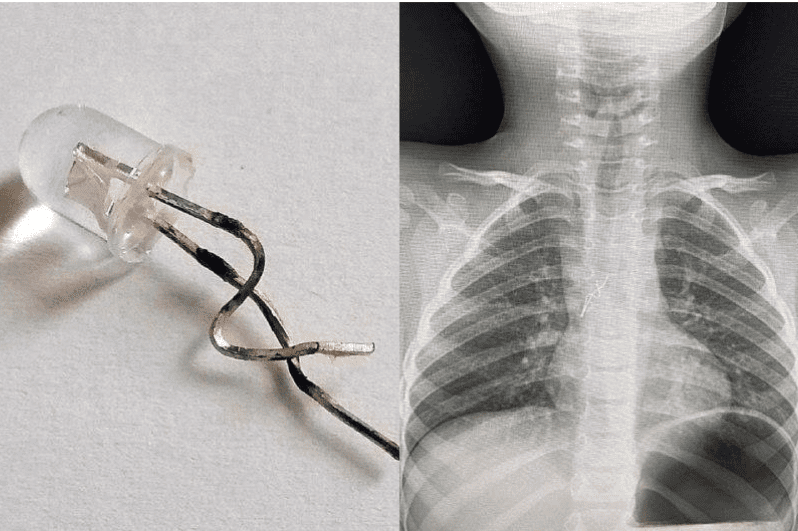

Как сообщается, четырехлетнего ребенка привезли в больницу, когда он уже не мог дышать. Сначала врачи сделали рентген, чтобы понять, где застряла деталь праздничной гирлянды. После этого медики избрали метод устранения проблемы. Для этого медикам не нужно было прибегать к хирургическому вмешательству и деталь удалось получить без разрезов на теле ребенка.

Часть гирлянды медики извлекали путем бронхоскопии. Такая процедура предполагает введение специального прибора в дыхательные пути человека через полость рта. Во время процедуры врач задел частичку детали, находившейся в бронхах ребенка, и без лишних повреждений трахеи и бронхи вытащил ее наружу.

Родители потерпевшего ребенка рассказывают, что такая ситуация произошла неожиданно. Ведь до этого их ребенок никогда не брал лишних вещей в рот и не имел такой привычки это делать. Однако когда они вытащили новогодние украшения, чтобы убрать елку, ребенок потянул светодиодную лампочку к губам и начал задыхаться.